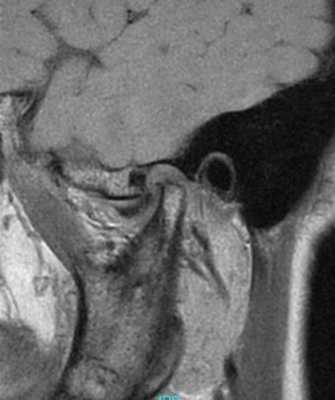

69-летняя пациентка с основными жалобами на боли в проекции челюсти, ограниченное открытие полости рта и невозможностью выдвинуть челюсть вперед обратилась за стоматологической помощью. Со слов пациентки ее симптомы начали развиваться около 6 месяцев назад: именно тогда она заметила, что ей трудно выдвигать челюсть вперед, чтобы посвистеть к своей собаки. По данным анамнеза на протяжении около 50 лет больная отмечала «выскакивание» и «пощелкивание» челюсти с левой стороны, и данные симптомы прекратились приблизительно в то время, когда ей стало трудно выдвигать нижнюю челюсть вперед. В ходе клинического осмотра было обнаружено, что максимальная величина межрезцового расстояния составляла 35 мм, при этом в ходе максимального открытия полости рта челюсть несколько смещалась влево. После массажа и растяжения левой жевательной мышцы и сустава снизилась интенсивность болевых ощущений, однако объем движений не увеличился. Таким образом был поставлен диагноз левостороннего смещения суставного диска без сопровождающейся редукции ВНЧС. Пациентка была направлена на магнитно-резонансную томографию (МРТ), и для исследования локализации и состояния диска при открытом и закрытом рте. Данные МРТ позволили установить, что с левой стороны отмечалось переднее смещение суставного диска в обеих положения, что также подтверждает диагноз смещения без редукции (фото 1-4).

Фото 3. МРТ-скан левого ВНЧС при закрытом состоянии рта: визуализация переднего смещения диска без редукции.

Фото 4. МРТ-скан левого ВНЧС при закрытом состоянии рта: визуализация переднего смещения диска без редукции.